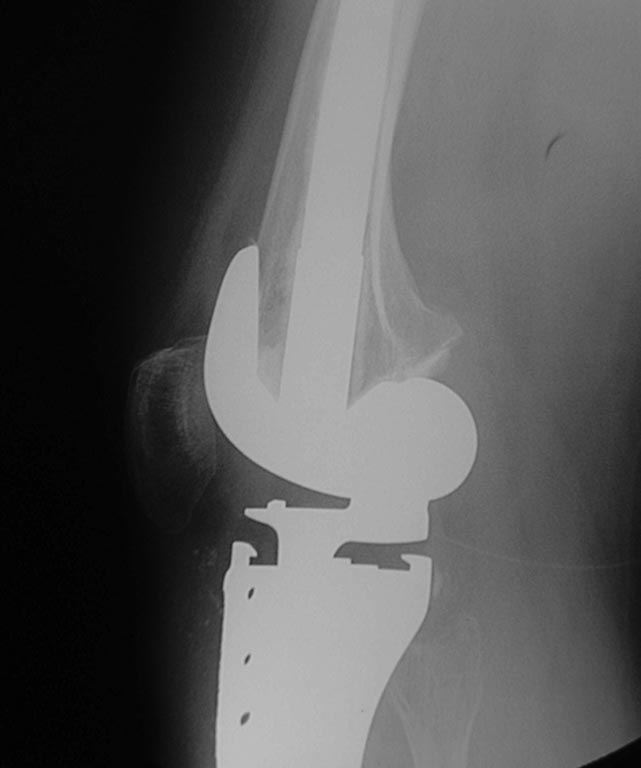

Уважаемые коллеги помогите с дальнейшей тактикой лечения.Больная 1976 г.р оперирована в октябре 2012 по поводу остеобластокластомы проксимального метафиза пр.большеберцовой кости модульным имплантом stryker

послеоперационное течение гладкое.Ходит с полной нагрузкой.Незначительно прихрамывая на пр.ногу .П/о рубец до 20 см без признаков воспаления Пальпаторно по передней поверхности метаэпифиза ю/берцовой кости .Активного разгибания нет ,и собственная связка надколенника не контурирует.Пассивные движения в полном обьеме.На контрольных рентгенограммах признаков нестабильности нет.В течении последних трех недель появилось по передней поверхности пр.голени серома.Пунктирована несколько раз – прозрачная синовиальная жидкость.Взята на посев –чуствительна к гентомицину,цефазолину ,цефтриаксону и левофлоксацину.В настоящее время получает цефазолин 1.0 в/м 3 раза и гентомицин 160 мг в/м 1 раз.(уже 5 дней)Динамики нет, жидкость продолжает скапливаться примерно в том же обьёме.